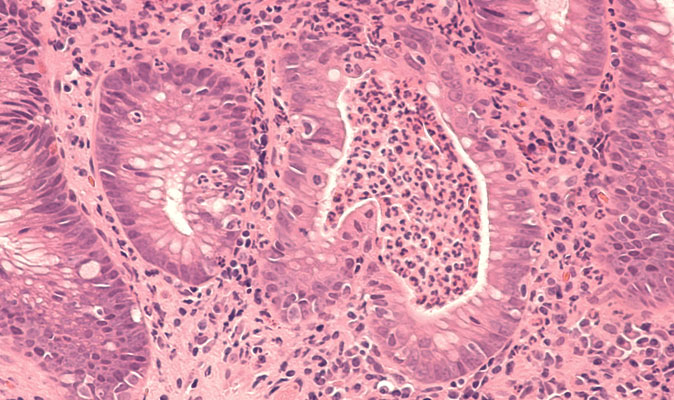

Es una exploración endoscópica en la cual se visualiza el intestino grueso y permite la identificación de los pólipos, que son los precursores del cáncer de colon.

A través de la colonoscopia se puede realizar una extracción de biopsia para determinar si se trata de cáncer de colon. Asimismo, también tiene carácter preventivo, ya que se pueden retirar los pólipos.